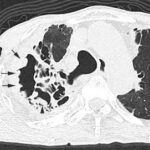

In patients with pulmonary aspergillosis, there is a high risk of haemorrhage. When this happens in the cavitary lesion, its wall shows lobulated thickening corresponding to fibrino-purulent material or to blood crust, therefore indicating a higher risk for...